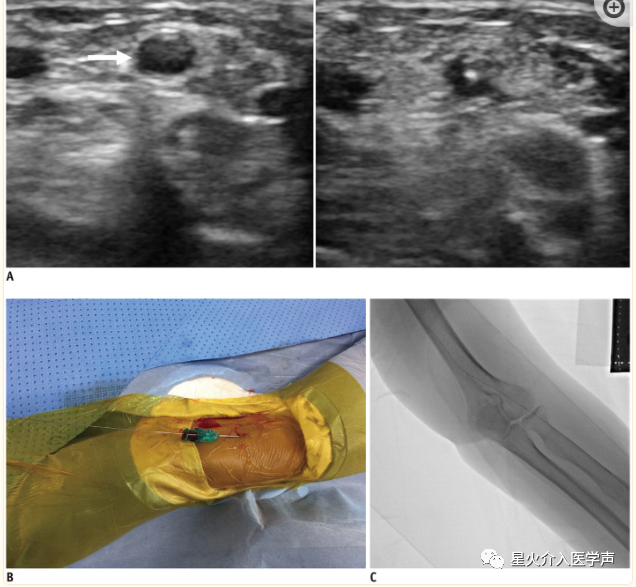

桡动脉通路

给予局部麻醉剂,在超声引导下用鞘管针穿刺桡动脉(图3).建议穿刺部位为桡骨茎突头侧2-3 cm。然后,将0.018英寸的导丝推入桡动脉。如果遇到任何阻力,将导丝拉回并重新调整进入。如果导丝无法推进,则进行透视查看。然后置入带有亲水涂层的专用桡动脉鞘。在我们的实践中,通常使用7 cm长的Prelude桡动脉鞘(Merit Medical Systems)。市售亲水性桡动脉鞘管见表1,根据Rathore等人的研究(25),使用亲水性鞘管可降低TRA期间桡动脉痉挛和疼痛的发生率。大多数诊断和介入手术可使用5-6-Fr鞘管进行。

3:桡动脉穿刺。

A.桡动脉直径(箭头)在超声图像上测量为 3.2 mm。在超声引导下,用 针穿刺桡动脉。B,C. 0.018 英寸的导线被推进到桡动脉。